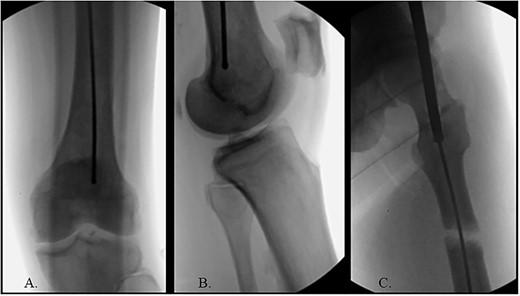

(A) AP radiograph of left hip with implant; (B) lateral radiograph of left hip with implant; (C) reduced fracture site with implant; (D) distal femur with implant.

The hip was extended, and a ball-tipped guidewire was successfully passed across the fracture site to a center–center positionwithin the canal at the level of the knee (Fig. 4C and D). Sequential 0.5-mm reaming from 9 to 13 mm prepared for an 11 × 400 mm, 125° Gamma3® intertrochanteric rod (Stryker© Kalamazoo, MI), with a 95-mm cephalomedullary screw and ×2 distal lateral to medial interlocking 5.0-mm screws (Fig. 5A–D). Through the course of the procedure, 400 cc of blood loss necessitated two units of packed red blood cells.